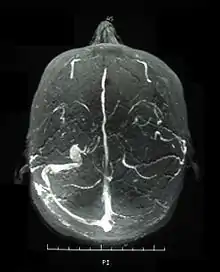

الجهاز العصبي

التهاب السحايا المزمن كتل في الدماغ، أو جذع الدماغ أو المادة البيضاء في النصف العميق للمخ، وقد تشبه تلك التي نراها في التصلب اللويحي . وقد نلاحظ ضمور في جذع المخ في الحالات المزمنة. تتراوح الأعراض من التهاب السحايا العقيم إلى تجلط الأوعية الدموية مثل جيب الام الجافيه "dural sinus" ، متلازمة المخ العضوية المتمثلة في نوبات، ارتباك، فقدان في الذاكرة.[6] غالبا ما تظهر في مراحل متقدمة من المرض ولكنها تكون مرتبطة بالتنبؤ الخاطئ لتطور المرض .

التهاب الأوعية الدموية المؤدي إلى انسداد الأوعية الدموية التي تمد العصب البصري قد يكون سبب اعتلال العصب البصري الحاد وضموره التدريجي في مرض بهجت .الفحص النسجي للحالات المصابة باعتلال العصب البصري الحاد أظهر وجود خلايا نجمية ليفية مكان محور العصب بدون أي تغيرات في الشبكية.[10] إصابة الجهاز العصبي قد تؤدي إلى ارتفاع ضغط الدم داخل الجمجمة بسبب تجلط الأوعية الدموية [8] و ضمور العصب البصري الثانوي لاحقا .

ظهور أعراض مرض بهجت ووجود آفات مخاطية جلدية بالتزامن مع فقدان حدة البصر والقدرة على رؤية الألوان قد يشير إلى إصابة العصب البصري . تشخيص المرض يعتمد على النتائج السريرية، بما في ذلك ظهور تقرحات الفم والأعضاء التناسلية والآفات الجلدية، مثل : حُمامَى عَقِدَة، حب الشباب، التهاب الجريبات، التهابات العين، و الأرجية المتعددة .قد ترتفع نسب علامات الالتهابات مثل ESR وCRP ( فحوصات للدلالة على وجود التهابات) . فحص العين الشامل قد يتضمن : فحص المصباح الشقي تصوير مقطعي للتماسك البصري للكشف عن فقدان العصب، فحص مجال الرؤية، استخدام الفندوسكوب لتقييم ضمور العصب وأمراض الشبكية، تصوير الأوعية باستخدام الفندوسكوب، تحفيز امكانية النظر، والتي توضح زيادة فترة التاخير . يمكن تحسين العصب البصري من خلال التصوير بالرنين المغناطيسي في بعض المرضى الذين يعانون من اعتلال بصري حاد، مع ذلك الدراسات لم تستبعد وجود اعتلال بصري. تحليل السائل الدماغي (CSF)قد يظهر ارتفاعاً في البروتين مع أو بدون خلايا السائل النخاعي، تصوير الأوعية قد يشير إلى وجود انسداد في الأوعية الجيبية؛ كسبب لارتفاع ضغط الدم داخل الجمجمة وضمور العصب البصري .